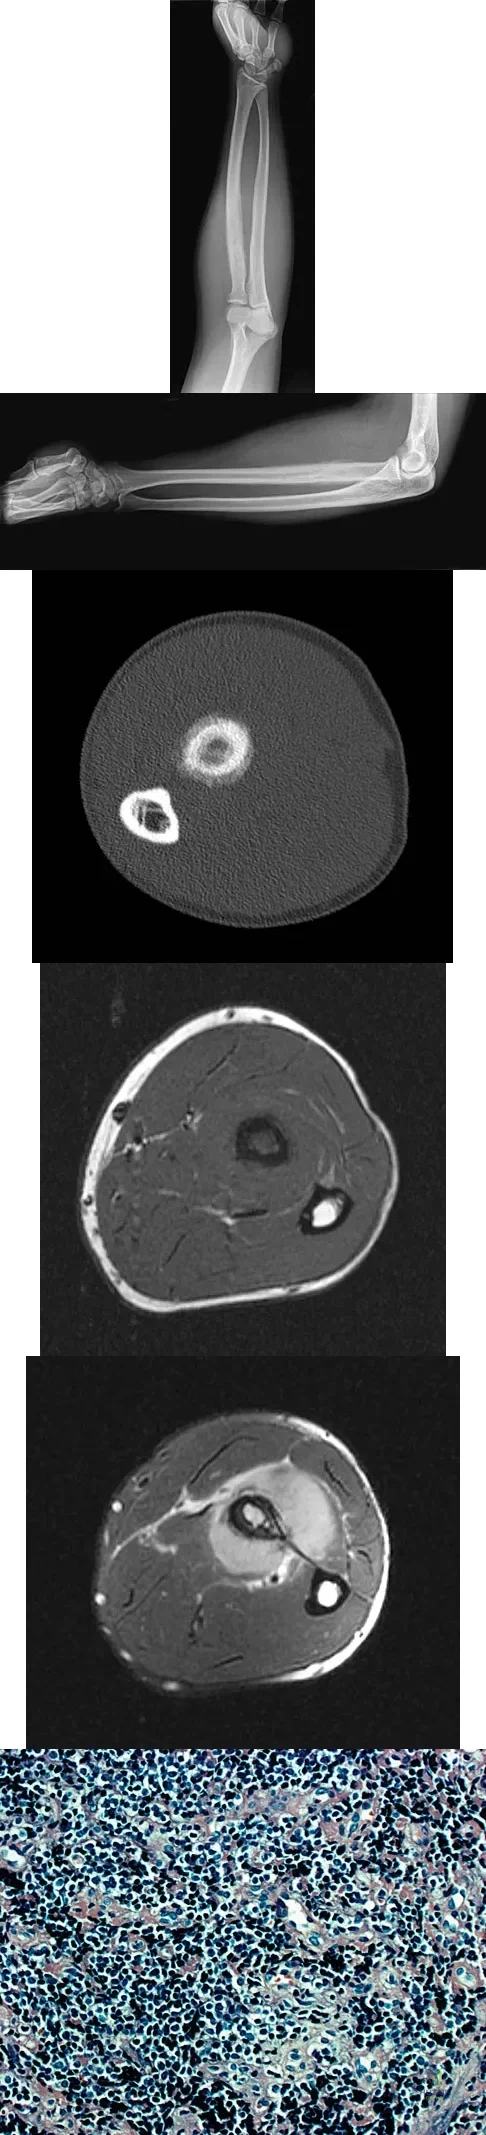

A 19-year-old man has had pain and swelling in his left forearm for the past 8 months. Laboratory studies show a mildly elevated WBC count and erythrocyte sedimentation rate. Radiographs are shown in Figures 58a and 58b, a CT scan is shown in Figure 58c, and T1- and T2-weighted MRI scans are shown in Figures 58d and 58e, respectively. A biopsy specimen is shown in Figure 58f. Immunohistochemistry demonstrates that the lesion is negative for leukocyte common antigen (CD34). What is the most common cytogenetic translocation associated with this lesion?

Explanation